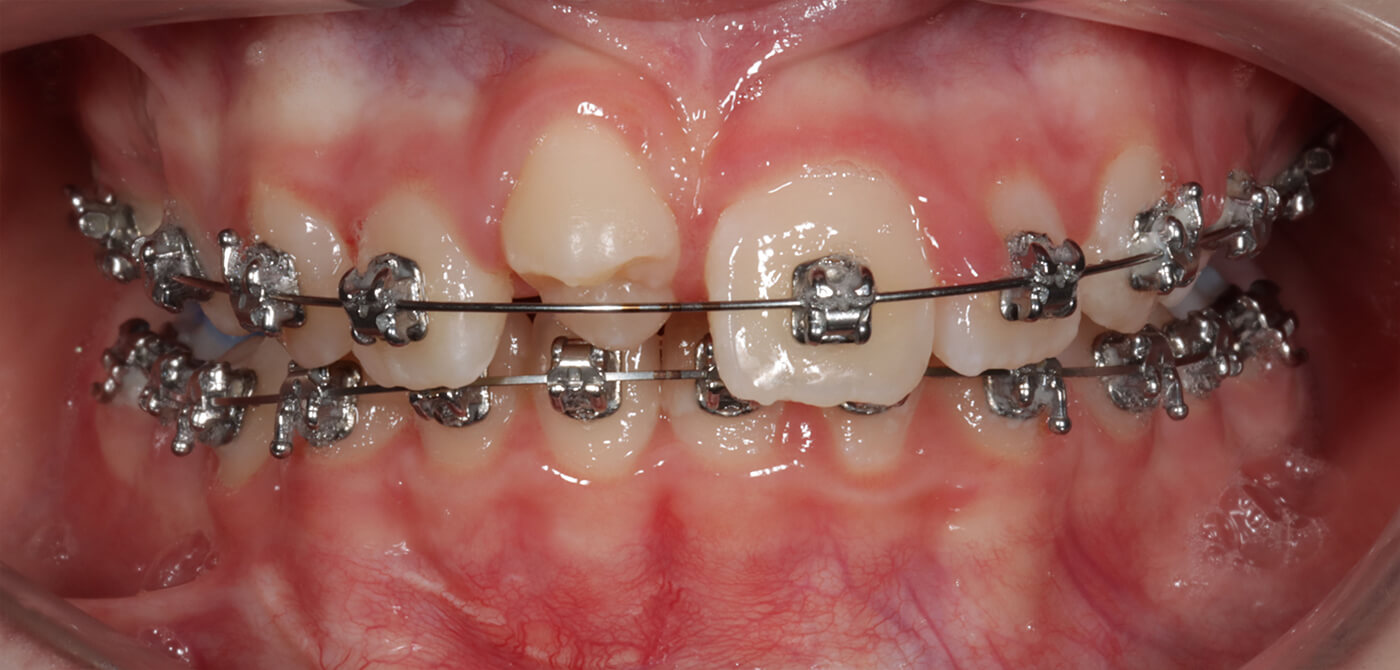

Situatie na autotransplantatie (foto door Proclin)

De behandeling voerden we uit in nauwe samenwerking met Proclin in Rotterdam. Ortho Fleur begeleidde het orthodontische deel van de behandeling, terwijl de autotransplantatie zelf werd uitgevoerd door dr. D.S. Barendregt van Proclin. Om de verplaatste kies zoveel mogelijk op een voortand te laten lijken, is deze door Proclin zorgvuldig opgebouwd met vulmateriaal.